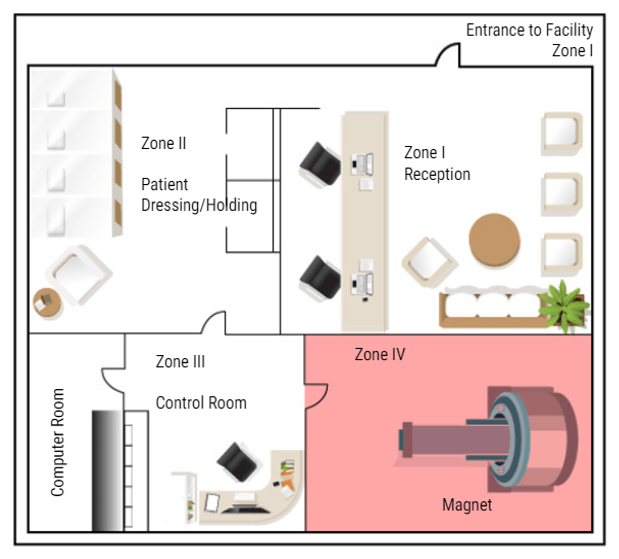

Now that we know what types of things to be concerned about in and around the MRI suite, we will now discuss MRI Zones and who can be in each zone.

Why Zones Are Important

In MRI we divide the work area into four zones. Each zone is very specific about who may enter and under what conditions. All zones must be marked in and around the MRI suite. There must also be a clear definition of where one zone ends and one begins, such as a doorway, chain/rope or another clearly visible sign. The signage should include who is allowed beyond that point. Let’s look at each zone:

Zone 1

Zone 1 is for the general public. Anyone can be in zone one. Some examples are hallways near the MRI area, the main waiting room, or a shared waiting area with other departments. There is NO screening needed to be in Zone One. While in zone one the patient may be asked to complete a screening sheet or be asked some basic safety questions before being moved to zone II.

Zone 2

Zone II is where a more thorough screening will take place. The patients will also be prepped for their scans in this area – changing clothes, removing all metal items and placing them in a safe place. Patients are only permitted to enter zone II when accompanied by a healthcare employee. Family members may also be permitted in Zone II accompanied by the healthcare worker without being screened. But this is the anyone not screened or cleared my go in the MRI area. ALL questions should be answered while the patient is in this area. Even if the patient has completed a screening form, they are not permitted beyond this point until they are cleared or accompanied by Trained MRI professionals.

Zone 3

The next zone is Zone three. This is the control area, where the MRI technologist would operate the scanner. Patients should be accompanied by an MRI safety trained individual to enter zone three. People who have not removed loose metals, or who have pacemakers or other unsafe medical devices, should not be permitted in zone III because of the proximity to zone IV. A screened but uncleared person may enter zone III ONLY under strict supervision by trained personnel, such as a patient who just wants to look at the MRI scanner to decide if they will be able to tolerate the exam.

Zone 4

The final zone is zone IV, the MRI scan room. ONLY CLEARED patients are permitted to enter Zone IV, accompanied by trained MRI personnel. The final step of clearance, while in zone III, should be to check the patient one last time for loose metals, other electronic devices and a last check of the critical screening questions. ACR suggests asking these questions a minimum of three times. Once At scheduling, once at screening and once at clearance. As an additional safety measure, many facilities build a metal detector into the doorway between Zone 3 and Zone 4. But there are hand-held devices that work well too and they are less expensive. Once the patient is cleared they can be taken into the MRI room and scanned.